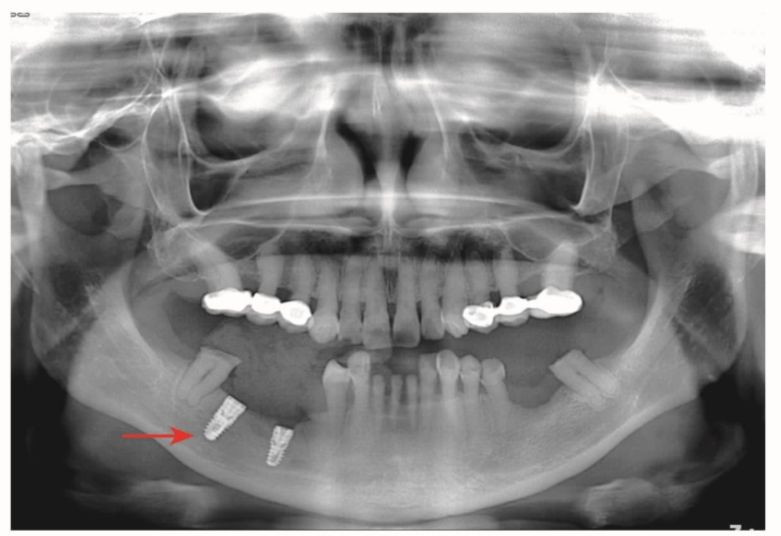

3 下牙槽神经管损伤

下牙槽神经管是下颌骨非常重要的结构,当下牙槽神经管损伤后会出现麻木或者其他的症状。误读全景片或者不了解全景片的失真率往往是造成手术意外的原因(图7)。

图7 全景片及CBCT冠状位A.全景片显示种植体压迫下牙槽神经管上壁;B.CBCT冠状位显示种植体进入下牙槽神经管内

对于全景片上神经管影像不清晰或者不能确定时,最好用CBCT检查,以确定神经管的位置,有没有其他分支,距离牙槽嵴的高度,颊舌侧的宽度以及有无颏孔舌侧开口等。在下颌骨骨量不足的情况下,种植手术时要高度警惕,尽量避免种植体进入下牙槽神经管(图8)。

图8 全景片显示C5、C6种植体进入下牙槽神经管

另外,过度追求种植体的长度也许是不科学和不明智的选择,损伤下牙槽神经管的风险是非常大的(图9)。

图9 全景片显示左侧D6种植体完全超过下牙槽神经管,D7种植体进入下牙槽神经管